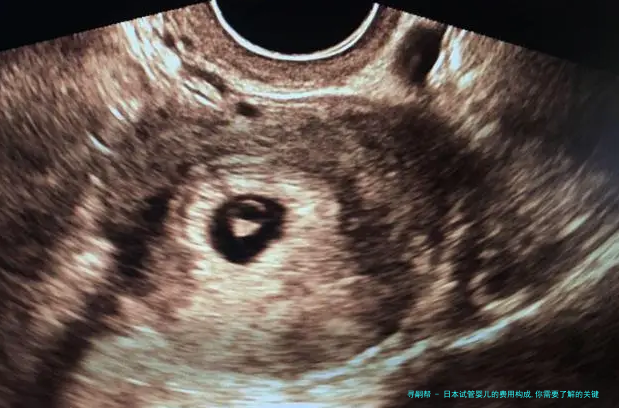

3. 手术费用:试管婴儿手术囊括、胚胎培育和胚胎移植等环节。手术费用约为3万至5万元。